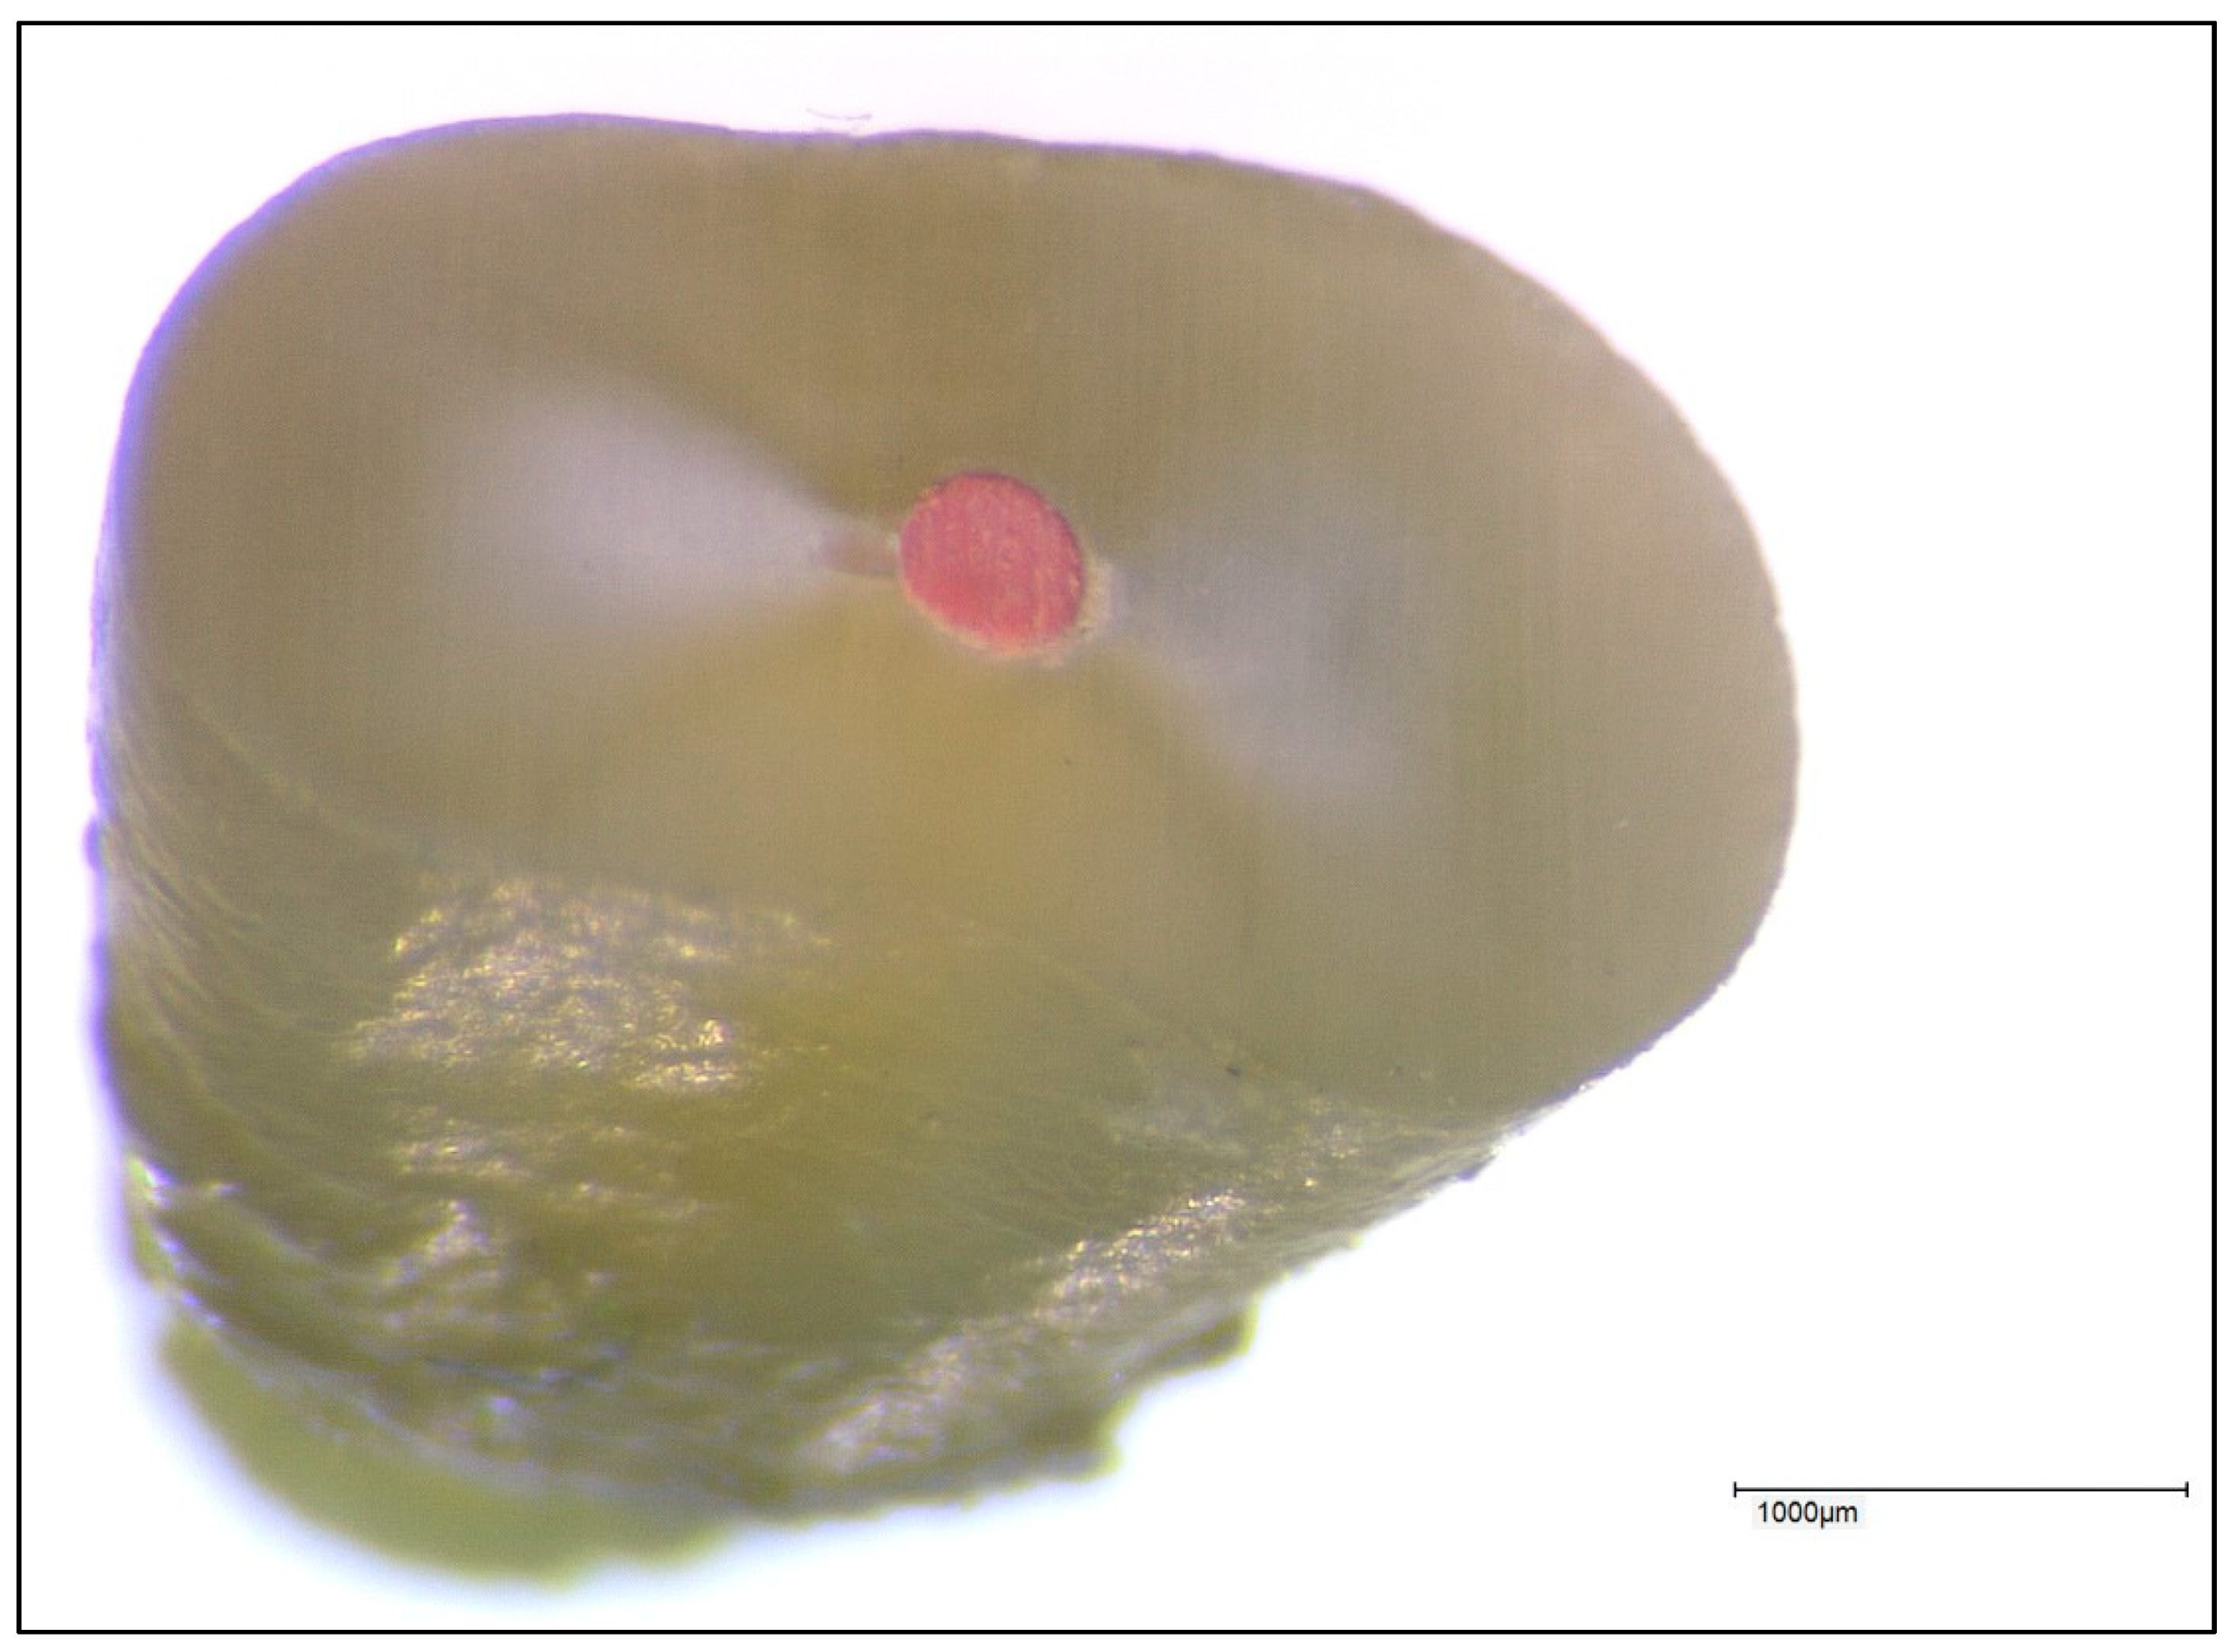

The same roots were used in the same sequence in each group. Any filling material present was completely removed from the root canal at the beginning of the experimental procedure, and the canal system was checked again for patency in each case. A representative image of a root specimen is shown in Figure 2.

Figure 2. Representative image of a root specimen used for leakage measurements.